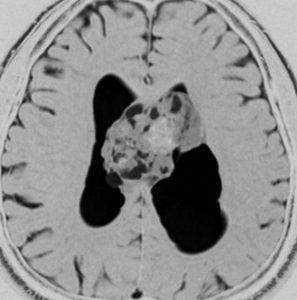

片側性水頭症

左尾状核から発生したものです。モンロー孔を閉塞して,片側性水頭症となっています。腫瘍がトリュフみたいにゴツゴツしているのも特徴です。

下のガドリニウム増強T1では,部分的に増強されます。

もちろん無症状ですが,年齢が若かったので全摘出しました。